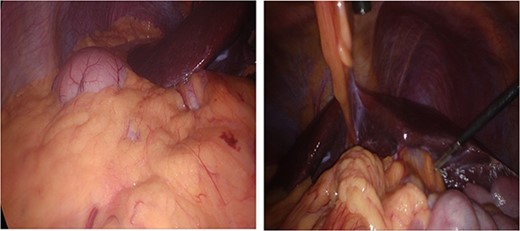

The patient was put under general anaesthesia and placed in the supine position. The operating surgeon and first assistant operating the camera stood on the patient’s right-hand side. The second assistant and scrub nurse stood opposite on the patient’s left. The laparoscopic stack and screen were positioned at the patient’s left shoulder. A 12 mm port was placed in the infra-umbilical position following open Hassan cut down, and pneumoperitoneum was achieved with CO2 at 14 mmHg and a flow rate of 5 LPM. One 11 mm port and two 5 mm ports were inserted under direct vision in an exact mirror image of a standard LC with normal anatomical positioning. This involved port placement as follows; 11 mm port in the subxiphoid area, 5 mm port in the left medial subcostal area, and a further 5 mm port in the left lateral subcostal area (Fig. 2). The patient was positioned with 30 degrees of head up and 20 degrees of left sided tilt. Upon insertion of the camera, it was imperative that we correctly orientated ourselves to the patient’s anatomy (Fig. 3).

Anatomical variation with anatomical left lobe of the liver and fundus of the stomach in right upper quadrant (RUQ) and gallbladder in left upper quadrant (LUQ).